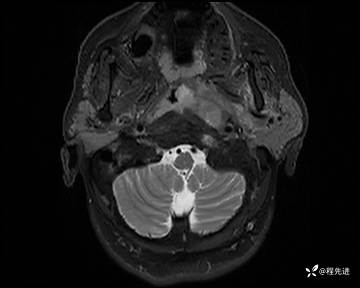

MRI平扫+增强:

T2压脂: